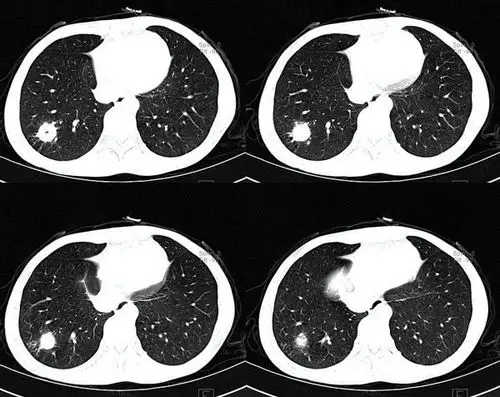

两肺散在实性肺结节,右肺胸膜下结核球

内壁和外壁均为圆形的空洞型结核球——潘军平老师

其中80%为良性包括:災性假瘤,错构瘤,结核球,真菌感染,硬化性肺细胞瘤